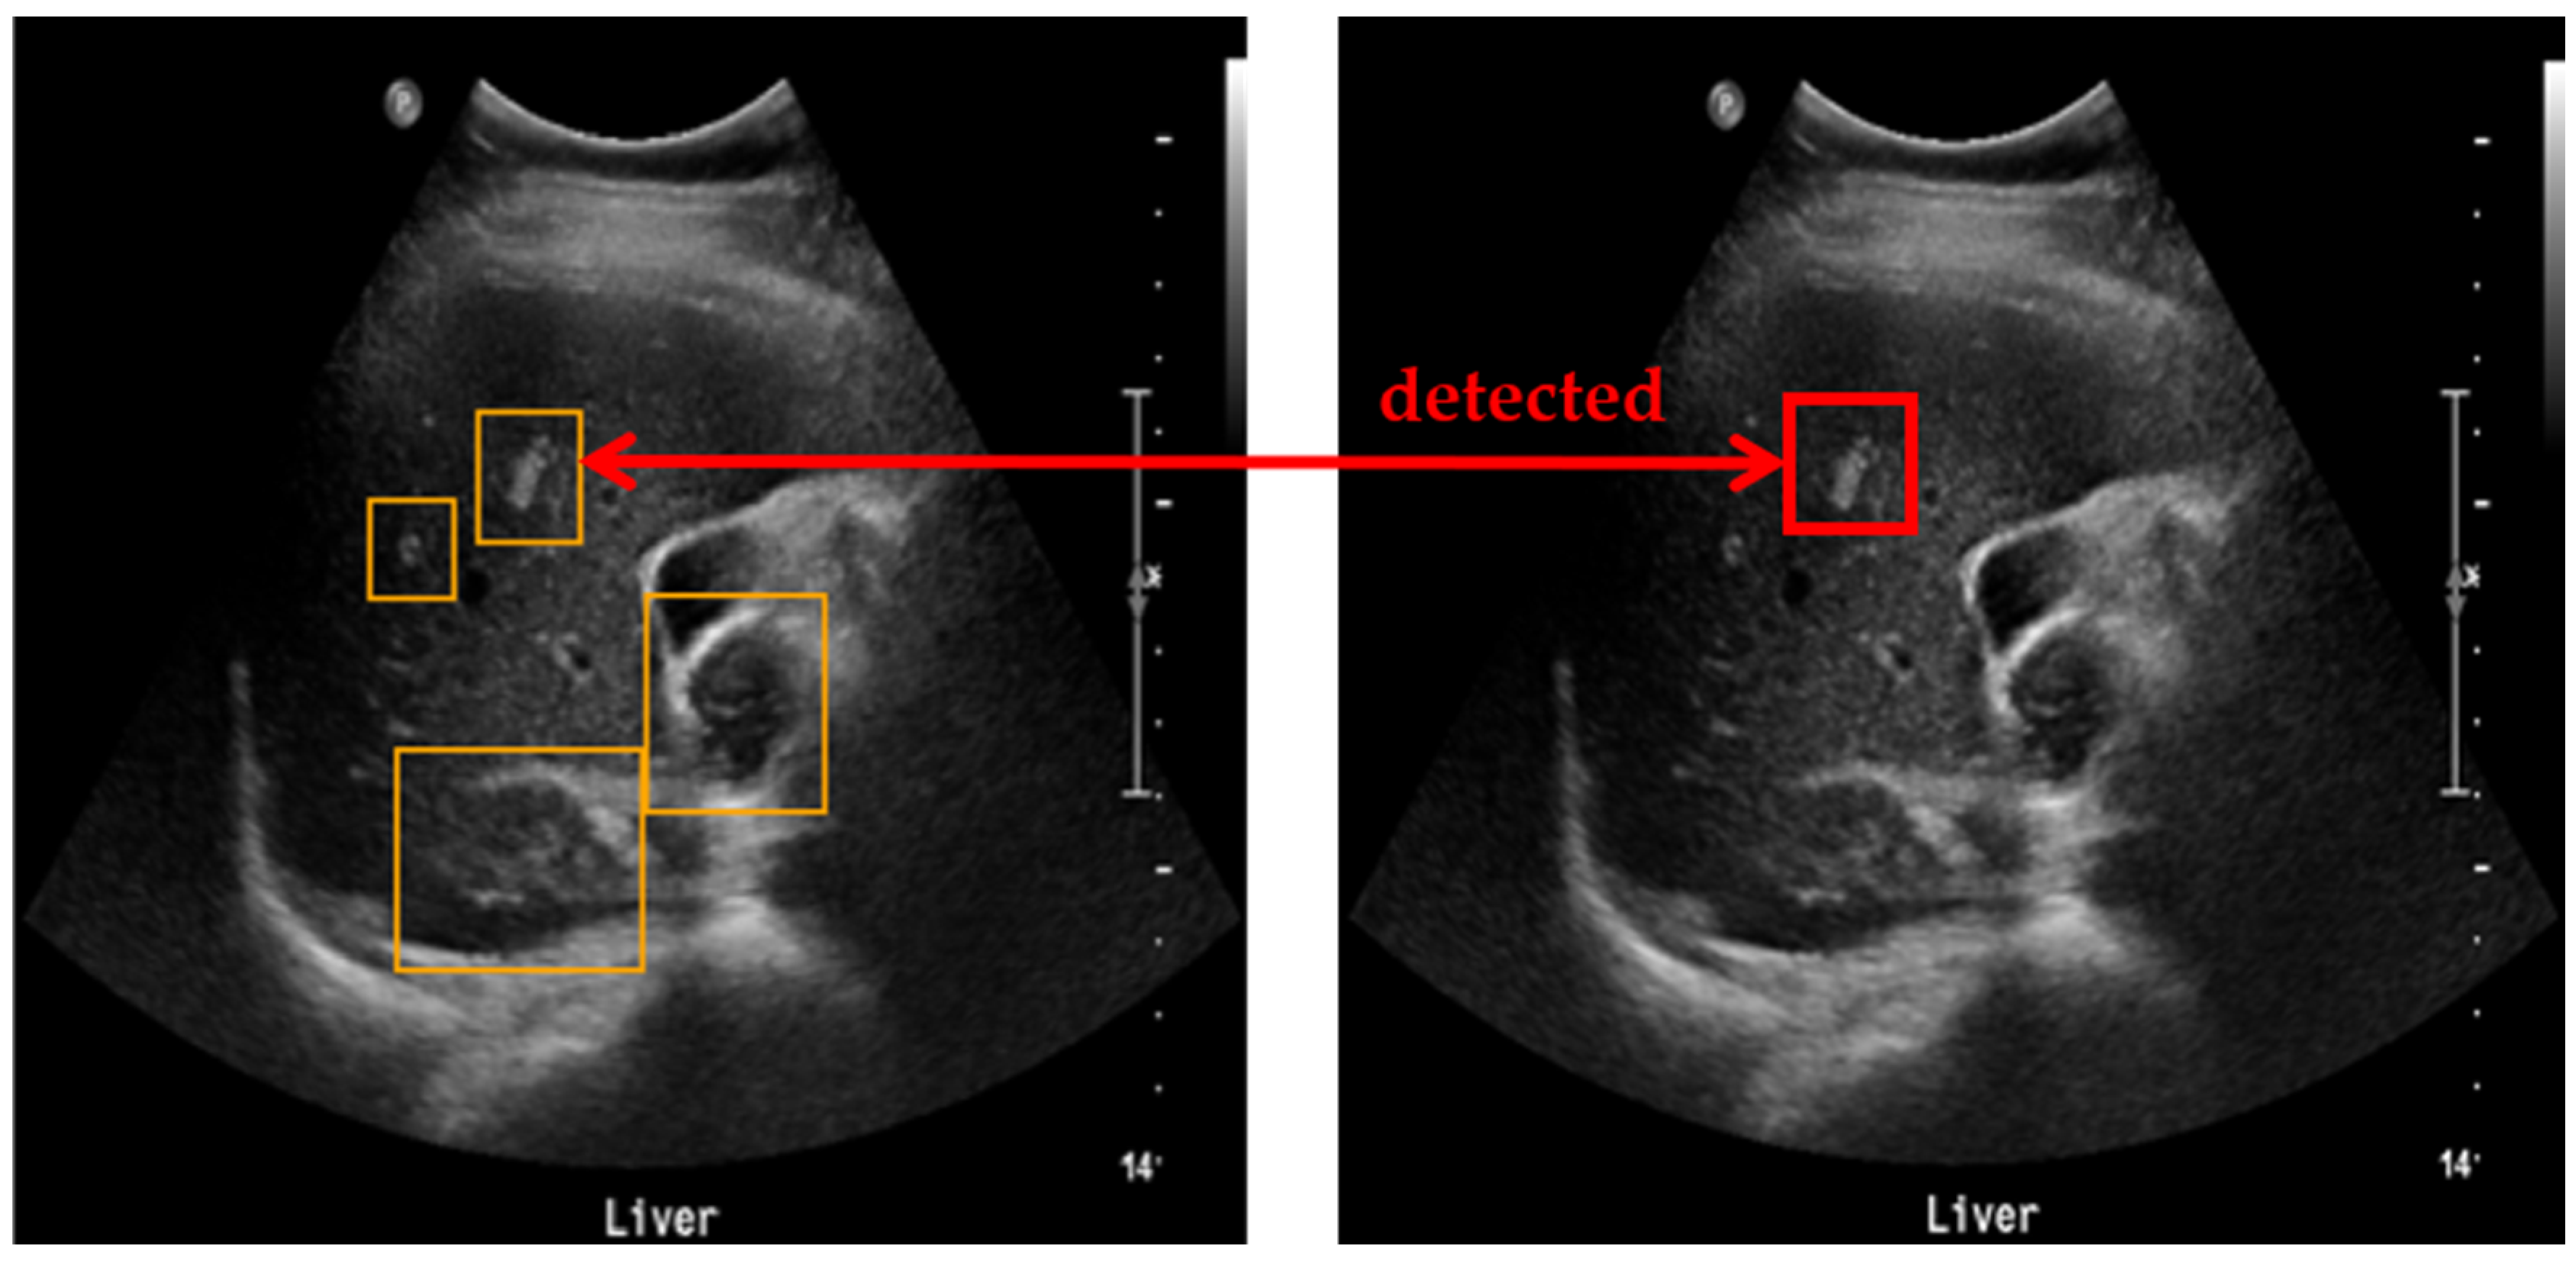

To evaluate the accuracy of lesion detection after applying clustering, SM-WBF, and padding, a novel measurement method was introduced. The primary goal was to ensure that all regions suspected of being lesions were identified, minimizing the chances of missing any lesions. As illustrated in Figure 5, all detected lesion-suspected regions were compared with the ground truth, and if at least one box matched, the detection was considered successful. A match was determined by comparing the IoU between the detected box and the ground truth box including padding. An IoU of 0.9 or higher was used as the threshold for a match, ensuring high precision in detection evaluation (Figure 6).

To evaluate the accuracy of the bounding boxes generated through clustering, SM-WBF, and padding, we calculated the detection success rate on the test data. A detection was considered successful if at least one detected bounding box matched the ground truth. The matching criteria were based on the IoU between the detected box and the ground truth box with the same padding applied. If the IoU was 0.9 or higher, the boxes were deemed to match. Detailed results are presented in the table below.

Figure 6. Method for measuring lesion detection accuracy. Among the four detected bounding boxes, at least one box has an IoU of 0.9 or higher with the ground truth, and, therefore, the detection is considered successful.